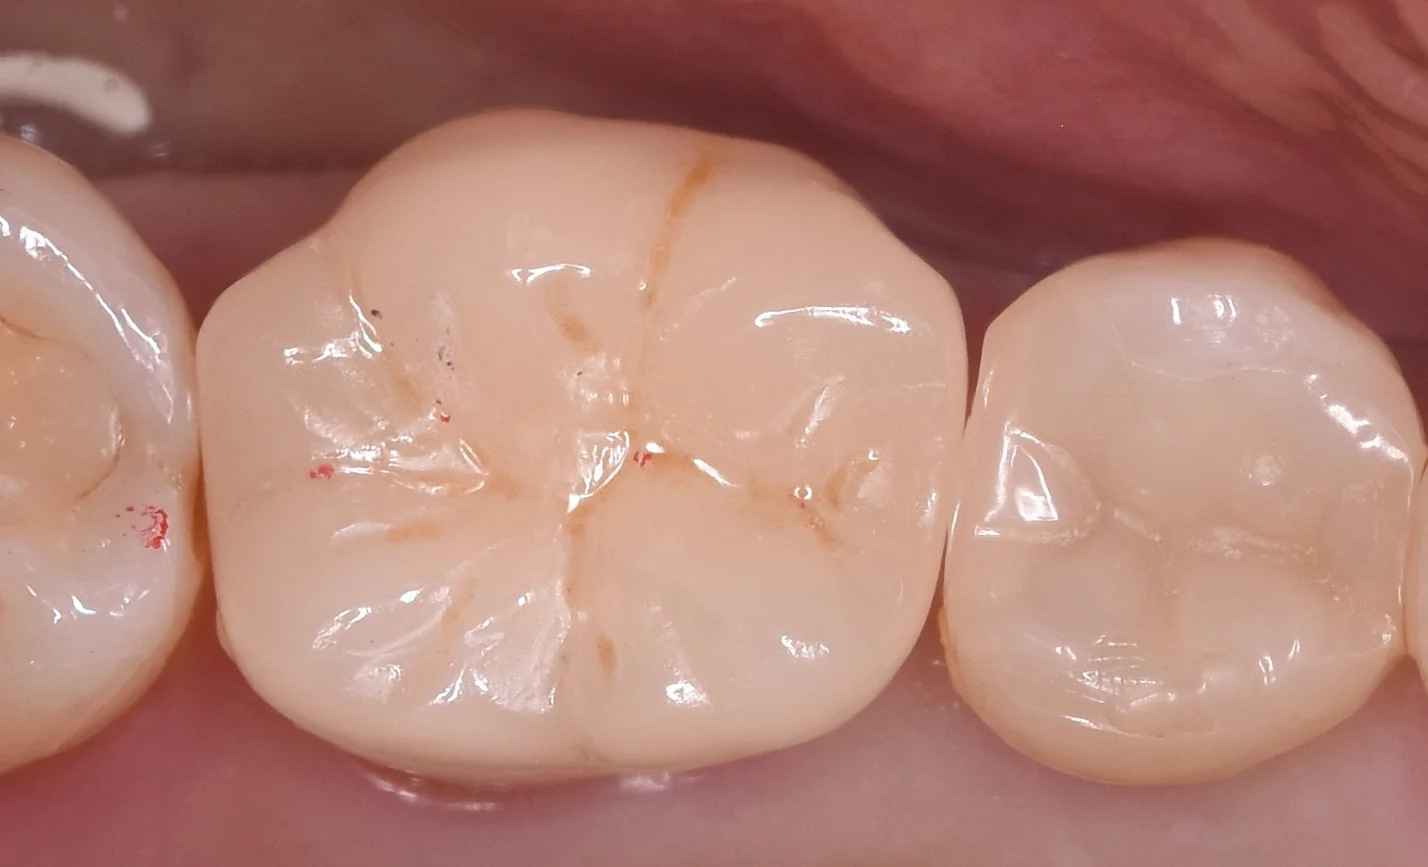

被せ物の調整を終え、Set直前の状態がこちらになります。

歯の色は前後の歯と調和しているのがわかるかと思います。